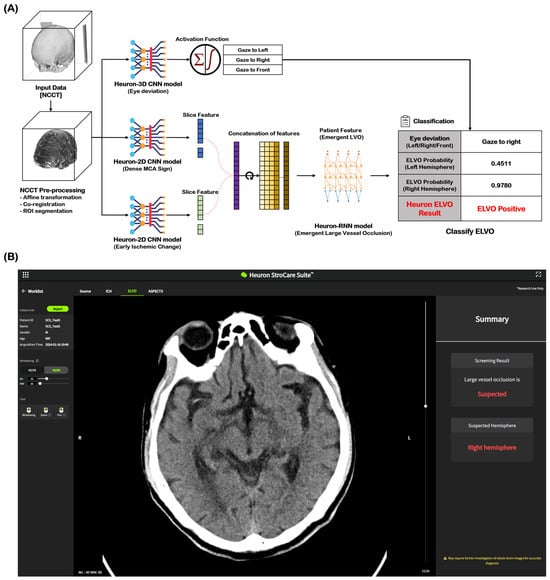

NCCT images of 2184 cases (ELVO: 1202 cases, non-ELVO: 982 cases) were used as the learning model for ELVO classification. The total cases were split in an 8:1:1 ratio for training, validation, and testing, respectively. In both the training and validation datasets for this model, any cases with the same registration ID from the same institution were excluded. Among the imaging biomarkers, HAS and EIC were identified by stroke experts and trained as ELVO imaging biomarkers. Eye deviation was independently identified and included in the learning model by detecting the deviation of the crystalline lens on NCCT. Figure 1A shows the Heuron ELVO process from input to output. After the preprocessed image was delivered to the convolutional neural network (CNN) model, Heuron ELVO identified the presence of eyeball deviation, HAS, EIC, and old infarct (OI). We employed class activation mapping to visualize region-specific feature contributions in NCCT scans, particularly for identifying occlusion patterns. These methods allow us to validate whether model decisions correlated with the radiological features of large vessel occlusions (e.g., hyperdense artery signs or early ischemic change). Subsequently, the features identified using the Heuron-2D CNN models were concatenated and input into the Heuron recurrent neural network model to classify whether ELVO was present, and a probability value between 0 and 1 was calculated. We applied Platt scaling to the validation set for probability calibration. The decision threshold was determined by selecting the point with the highest Youden’s J statistic (J = sensitivity + specificity − 1J = sensitivity + specificity − 1) on the ROC curve (Shown in Figure S1 and Table S1). Figure 1B shows an example of a Heuron ELVO output presented to clinicians.

Figure 1.

Automatic ELVO classification based on the Deep Learning model. (A) Inference flow for classifying patients with emergent large vessel occlusion, and (B) an output example of a suspected ELVO case in Heuron ELVO. ELVO, emergent large vessel occlusion; NCCT, non-contrast computed tomography; ROI, region of interest; CNN, convolutional neural network; MCA, middle cerebral artery; RNN, recurrent neural network.